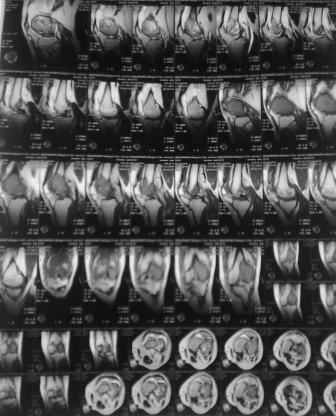

Уважаемые коллеги! Добрый вечер! Обратился мужчина 32 лет с жалобами на боли в обл. внутреннего мышелка левого бедра. Боли беспокоят около шести месяцев, лечился дома всякими мазями и т.д. 2 неделя назад упал , и после этого боли с каждым днем усиливаются. Местно определяется резкая болезненность в обл. мышелка бедра, явление не выраженного синовита, ограничение движения в коленном суставе, мягкотканый компонент опухоли не определяется, лимфоузлы не увеличены,Р-скопия легких без патологии,клинико-биохимические анализы в пределах нормы. Гистология- гигантоклеточная опухоль. Направил в онкологический центр, рекомендовали резекцию и ревизионное эндопротезирование коленного сустава, от которого больной отказался и опять вернулся к нам, временно фиксировали гипсовой повязкой. Уважаемые коллеги можно ли помочь больному, т.к. на практике были, что после перелома опухоль рассосалась и переломы срослись! Или может быть аутопластика и фиксация перелома? С уважением Абдурашид.

В доступной литературе мы не нашли подтверждения о спонтанном выздоровлении после (ОБК)- гигантоклеточной опухоли. В большинстве случаев данное заболевание путают с костной кистой, и грамотно проведенная дифференциальная диагностика поможет выбрать правильное решение.

Для костной кисты характерны более молодой возраст, овоидная форма, меньший размер, строго по оси, опухоль локализуется не в эпифизе, а в метафизе, поверхность гладкая, на 15% чаще чем при гигантоклеточной опухоли случаются патологический переломы. При патологических переломах тормозится дальнейший рост кисты и проблем со сращением не бывает.

Форма гигантоклеточной опухоли, вследствие ограничения ее роста суставной щелью, полуовальная или полуверетенообразная. Располагается асимметрично, крупноячеистая, размеры опухоли больше, густо костные балки, менее прозрачная на рентген снимках и на срезе грубо бугристая с продольными углублениями, как от сухожилий мышц.